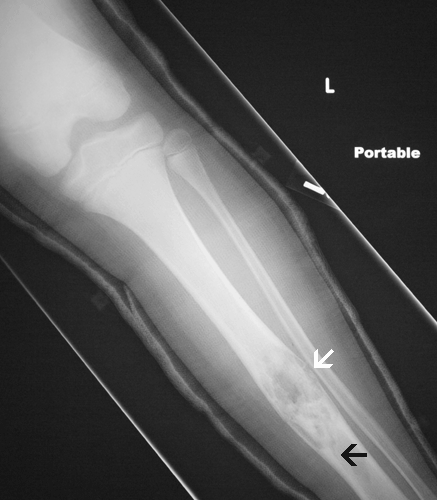

Clinical information: The patient is an 12 year old boy who presented to the emergency room with pain and swelling of the left leg. He first experienced the symptoms while practicing football. An X-ray was performed (Panel A) revealing a pathologic fracture through the shaft of the left tibia. The fracture was associated with a large soap bubble-like lesion in the middle diaphysis. A curettage biopsy was performed.

Radiology of the case: On the plain film, there is an osteolytic lesion (Panel A) associated with a fracture (fracture line is illustrated by the black arrow). The lesion is predominantly intracortical. However, the cortex is thinned out significantly in some areas and is breached (white arrow). The medullary cavity is also involved.